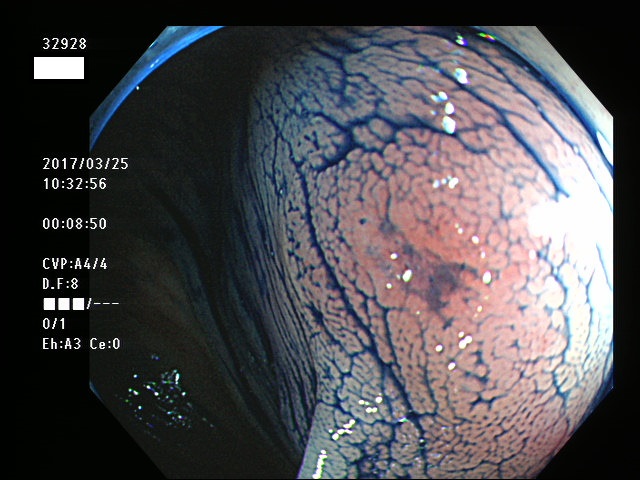

上記100名より抽出した平坦・陥凹型腺腫(=癌化の危険が高いが見落としやすい病変)の内視鏡写真

32901 32902 32903 32904 32905 32906 32907 32910 32911 32912 32915 32916 32918 32919 32920 32921 32922 32923 32924 32925 32926 32927 32928 32929 32931 32933 32935 32939 32941 32951 32953 32956 32957 32959 32961 32963 32964 32965 32967 32968 32971 32972 32973 32976 32978 32980 32981 32982 32986 32988 32989 32990 32994 32995 32998・・・・・・の55名